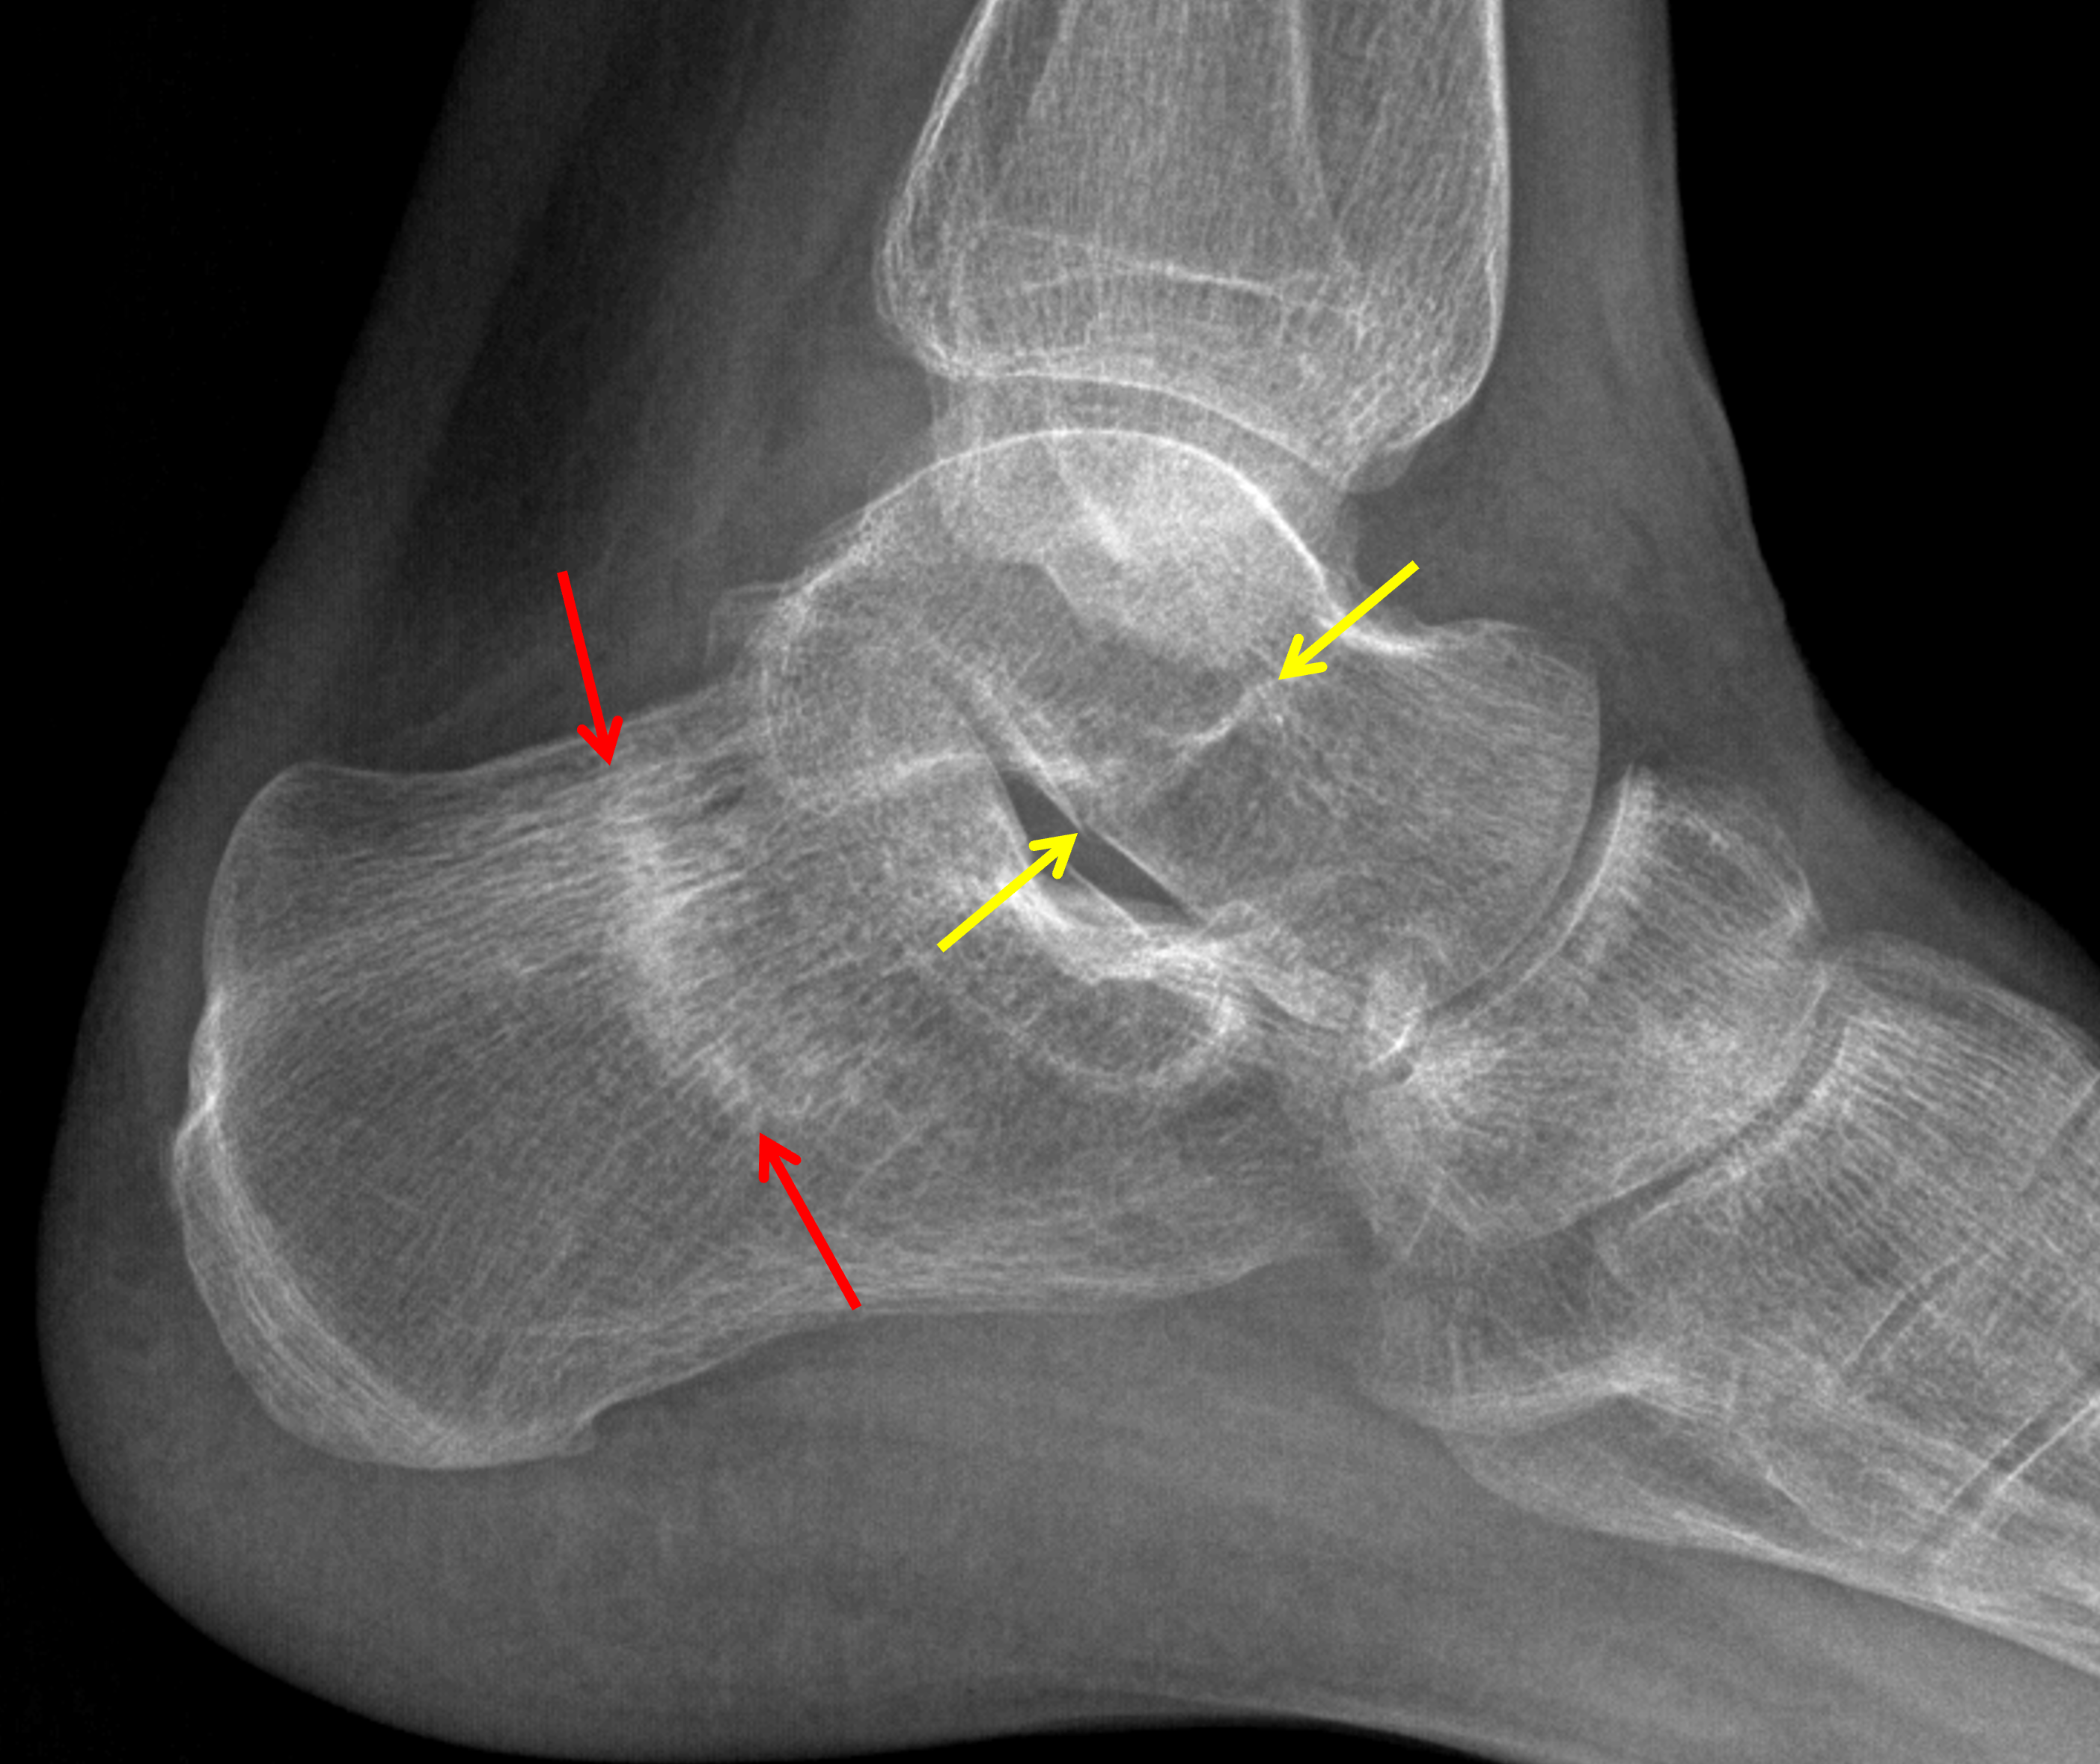

• Acute oblique minimally displaced fracture of the lateral malleolus with medial extension to the level of the tibiotalar joint

• Linear band of sclerosis in the calcaneus

• Linear sclerotic band extending through the talar neck with possible minimal cortical offset along the inferior margin, only seen on the lateral view

• Calcaneal stress fracture

• Weber type B ankle fracture

• Possible talar neck stress fracture

Acute oblique minimally displaced fracture of the lateral malleolus with medial extension to the level of the tibiotalar joint (Weber B).

Mild medial clear space widening raising concern for associated deltoid ligament injury.

Linear band of sclerosis in the calcaneus concerning for calcaneal stress fracture.

Linear sclerotic band extending through the talar neck with possible minimal cortical offset along the inferior margin (only seen on the lateral view), concerning for a talar neck stress fracture.

Red arrows: calcaneal stress fracture. Yellow arrows: possible additional stress fracture involving the talar neck.